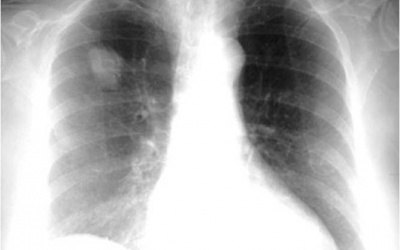

Bệnh viện Nhi trung ương đã tiến hành thành công kỹ thuật ECMO (phương pháp oxy hóa qua màng ngoài cơ thể) cho bệnh nhân được chẩn đoán ARDS (hội chứng suy hô hấp cấp tiến triển) trên...